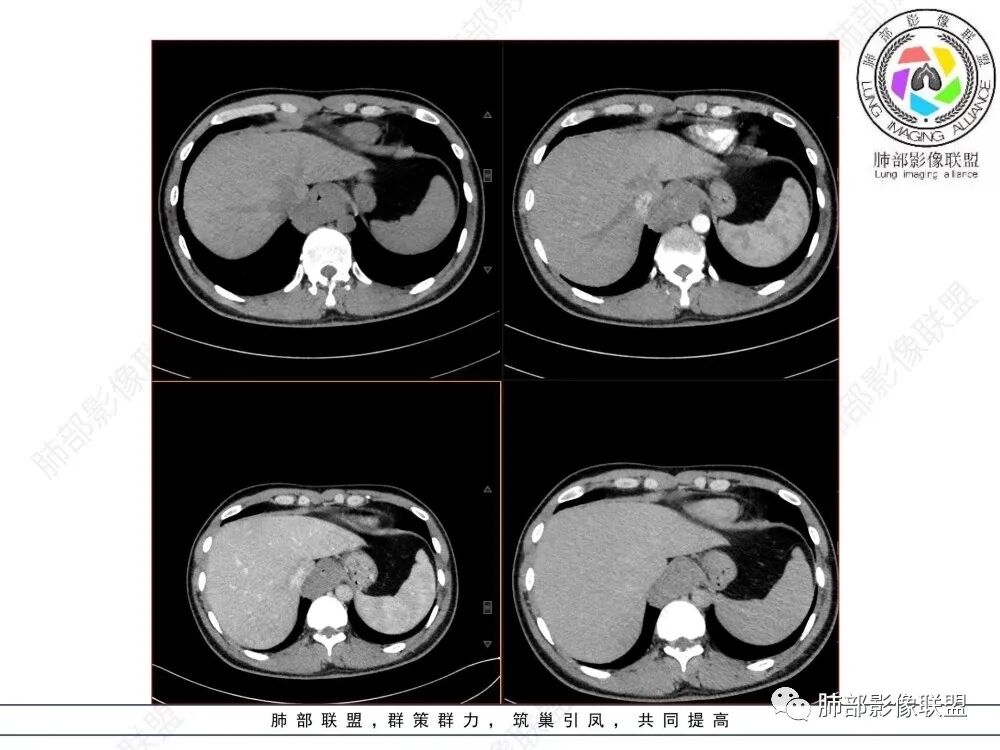

青年人,食管来源肿瘤性病变,平扫密度均质,病灶边缘分叶,食管部分僵硬,增强病灶轻中度强化,强化不愠不火,考虑恶性,淋巴瘤,鉴别食管平滑肌瘤,间质瘤。

食管下段近贲门处肿块,食道受压变窄,粘膜无破坏,轻度强化,T2等低信号,考虑平滑肌瘤?神经鞘瘤?鉴别间质瘤。

年轻男性,食管下段占位性病变长轴平行于食管,平扫密度尚均匀,增强轻度强化,MRI示T1、T2低信号,DWI低信号。考虑来源于食管,考虑平滑肌瘤或神经鞘瘤>间质瘤

平滑肌瘤(食管下段团块状肿块,环食管生长,分叶密度均匀,增强轻度强化。钡餐时食管受压移位,T1 T2 DWi低信号,病变来源于食管,考虑平滑肌瘤)

食管下段肿块,环壁生长,有分叶状,密度比较均匀,考虑食管粘膜下肌瘤。

食管下段后壁团块状肿块,管腔受压,密度均匀,增强轻度强化,食管受压移位,考虑平滑肌瘤,鉴别间质瘤。

食管下段肿块,管腔受压变窄,密度均匀,增强轻度延迟强化,考虑平滑肌瘤,鉴别间质瘤。

食管平滑肌瘤是最常见的食管良性肿瘤,多见于男性,男女之比为2.6:1,高发年龄 30~60岁之间与食管癌相比,食管平滑肌瘤 的一个主要特点是病史相对较长,病情进展缓慢。病史最长者达10年余,平均 15.7个月,尽管病史较长,但大多数患者仍能进普食。食管平滑肌瘤的诊断一般比较容易,结合患者临床症状、食管造影及食管镜所见,一般均能得出正确诊断。食管造影主要为充盈缺损,病变与食管壁成锐角,粘膜线连续无破坏,管腔收缩扩张比较自如。钡餐造影敏感性高,但对食管壁间及食管周围情况难以判断。CT具有极高的密度分辨率,并且可以获得高质量的多平面重组图像,有利于食管壁间及食管周围情况的判断,表现为食管下段环绕管壁生长,偏心性或薄厚不均软组织密度肿块,密度均匀,内缘分叶状,管腔与正常食管壁构成不规则多角形扩张,增强动脉期无强化,多角度重建其病灶长轴与食管长轴不一致。由于食管壁在收缩状态下厚度约为5.6mm,扩张状态厚度不超过3mm,CT扫描时保持食管处于扩张状态可提高小病灶检出率。MR表现为T1加权等信号,T2加权稍高信号,可见高信号粘膜层,增强扫描轻度渐进性强化,密度均匀,无出血坏死。对于粘膜及周围脂肪间隙的判断具有明显优势。